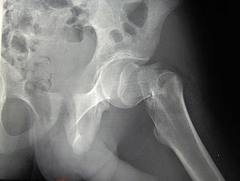

- Femoral Osteotomy – commonly used for adults in the treatment of hip fracture nonunions and malunions (earlsview.com)